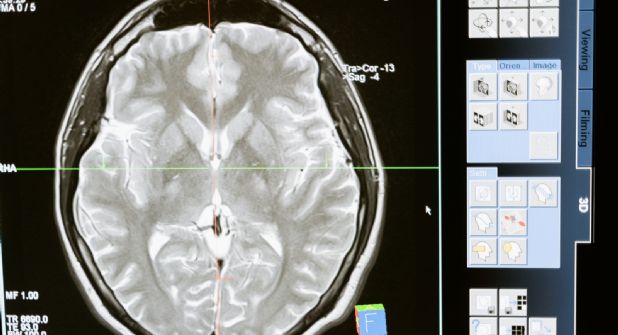

BARCELONA.- Científicos de un equipo internacional liderado por el Instituto de Investigación Biomédica de Bellvitge (IDIBELL), en Cataluña (noreste), han identificado el gen PI4KA como causante de una nueva enfermedad neurológica minoritaria que provoca un retraso global en el desarrollo del cerebro, epilepsia y defectos en la mielina y el sistema inmune, entre otros síntomas.

El gen implicado en este nuevo trastorno "es muy importante para la formación de la mielina, una sustancia vital para la conducción de los impulsos eléctricos entre las neuronas", explica la investigadora y genetista Aurora Pujol, que ha liderado el estudio.

"Una mielinización incorrecta hace que los nervios no puedan dirigir bien las señales hacia el cerebro ni a la inversa, como ocurre en la esclerosis múltiple, y que, por ejemplo, no se puedan enviar correctamente mensajes como mover una pierna", añade.